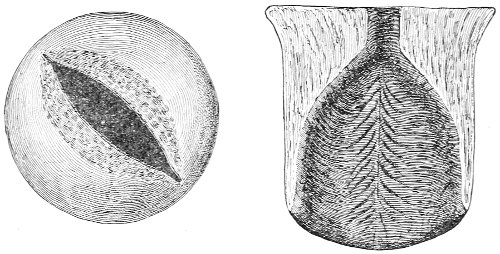

The vagina extends, as a transverse slit in the pelvic floor, upward and backward, approximately in the direction 60 of a line drawn from the ostium vaginæ to the fifth sacral vertebra. It is approximately parallel with the conjugate of the brim, so that when the woman is erect the long axis of the vagina is inclined at an angle of 60° to the horizon. The vagina is not a vertical open tube: it is a slit in the pelvic floor, in health always closed by the accurate apposition of the anterior and posterior walls (Fig. 21). The anterior vaginal wall is about 2½ inches long in a vertical mesial line. The posterior vaginal wall is about 3½ inches long. The vaginal walls are triangular in shape, being broader above than below. The shape of the normal vagina at the pelvic outlet is shown by Fig. 23. The section here shows the vaginal 61 slit of the shape of the letter H. The portions of the slit extending backward and somewhat outward are called the vaginal sulci or furrows. They are directions of diminished resistance in which tears are liable to occur.

Fig. 23.—Section illustrating the characteristic form of the vaginal cleft (Henle): Ua, urethra; Va, vagina; L, levator ani; R, rectum.] 62